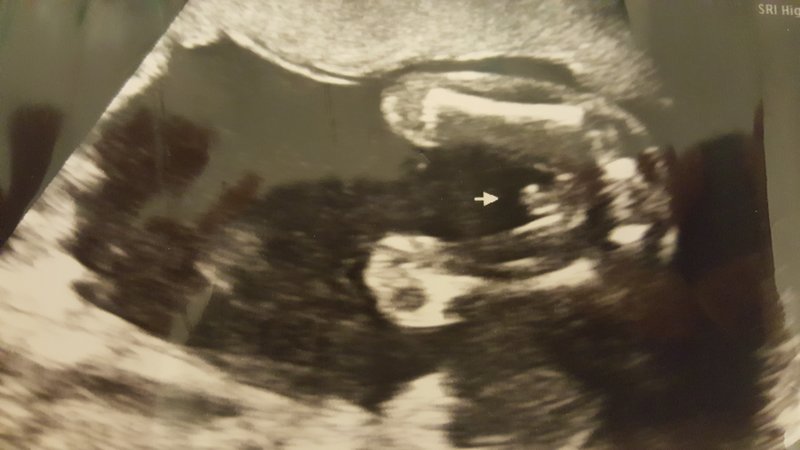

Here is my 19 week ultrasound picture. Could this be the cord instead of a penis? Has anyone else had a picture like this and it turned out to be a girl? ThanksAttachment 35821Attachment 35821